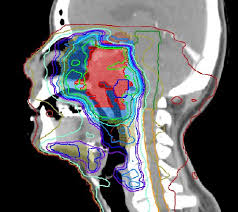

2. العلاج الإشعاعي

يعتمد على استخدام أشعة عالية الطاقة لتدمير الخلايا السرطانية. يمكن استخدامه:

• قبل الجراحة لتقليص حجم الورم.

• بعد الجراحة للقضاء على الخلايا المتبقية.

• كعلاج رئيسي لبعض الأورام مثل سرطان البروستاتا.

تشمل تقنيات الإشعاع الحديثة:

• العلاج الإشعاعي الخارجي.

• العلاج الإشعاعي الموضعي (Brachytherapy).

• العلاج بالبروتونات لتقليل تلف الأنسجة السليمة.